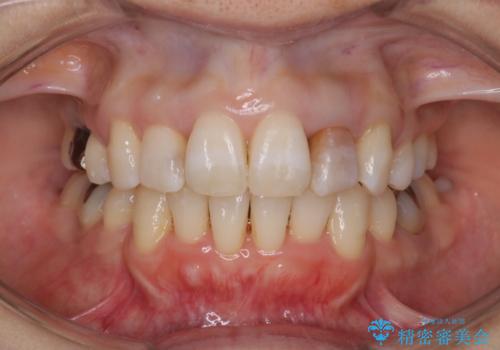

前歯のクロスバイト ワイヤー装置を併用したインビザライン矯正

担当医 藤巻太一朗